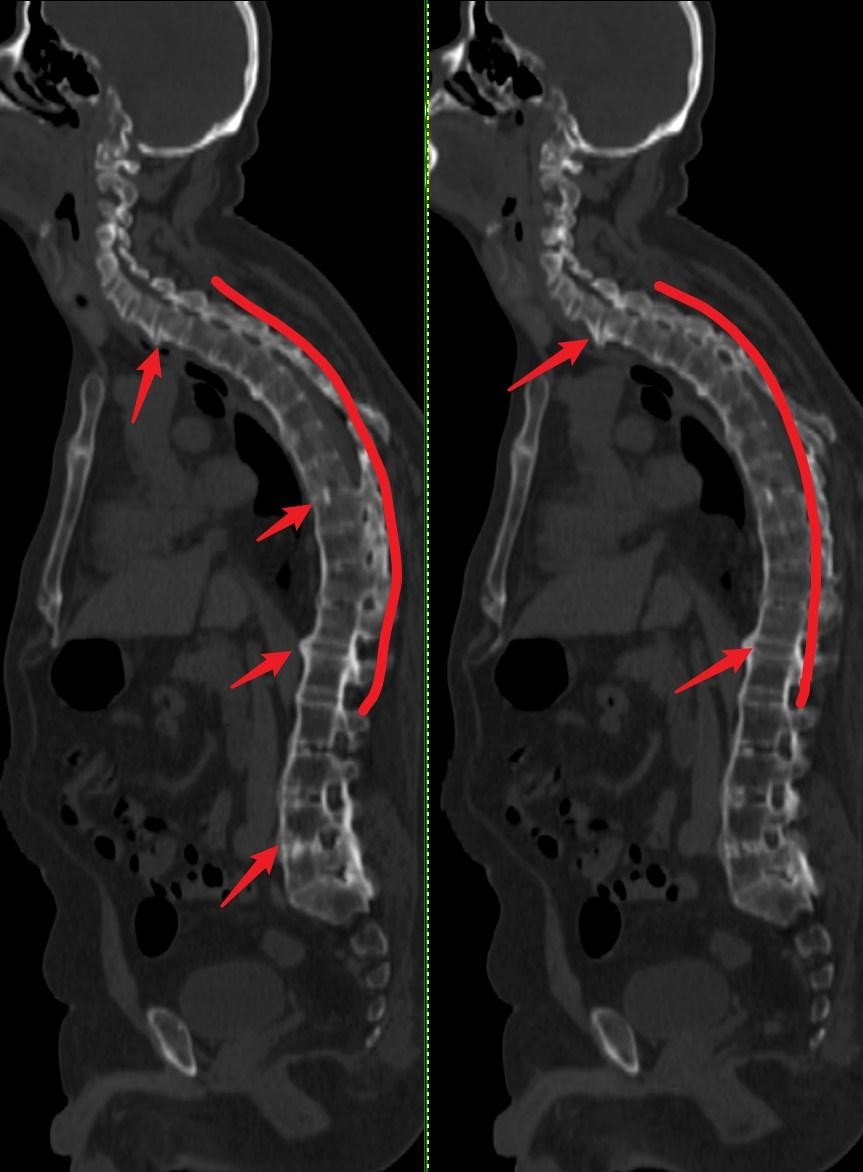

图3:较前一位患者严重↓

病变累多个椎体,脊柱呈竹节样改变,脊柱后凸更为明显。↓